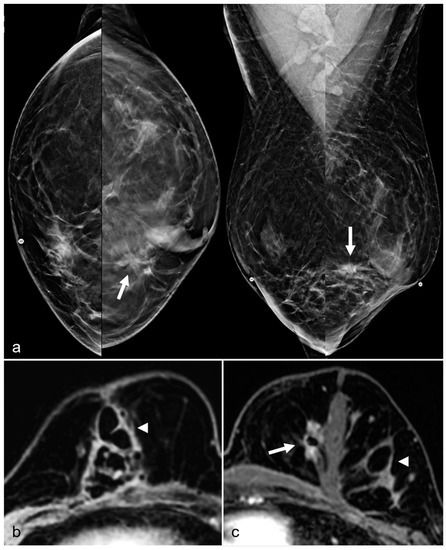

Global asymmetry is described as a large amount of fibroglandular density tissue over a substantial portion of the breast and judged relative to the corresponding area in the contralateral breast. BES can cause global asymmetry in the bilateral breasts due to differences in the granulation response of the breast tissue after surgery (Figure 2).

Figure 2. A 79-year-old woman with BES changes. Bilateral CC (above) and MLO (below) views demonstrate more dense tissue from post-BES changes on the right (ovals) compared to left breast. Note that right breast is smaller than the left breast.